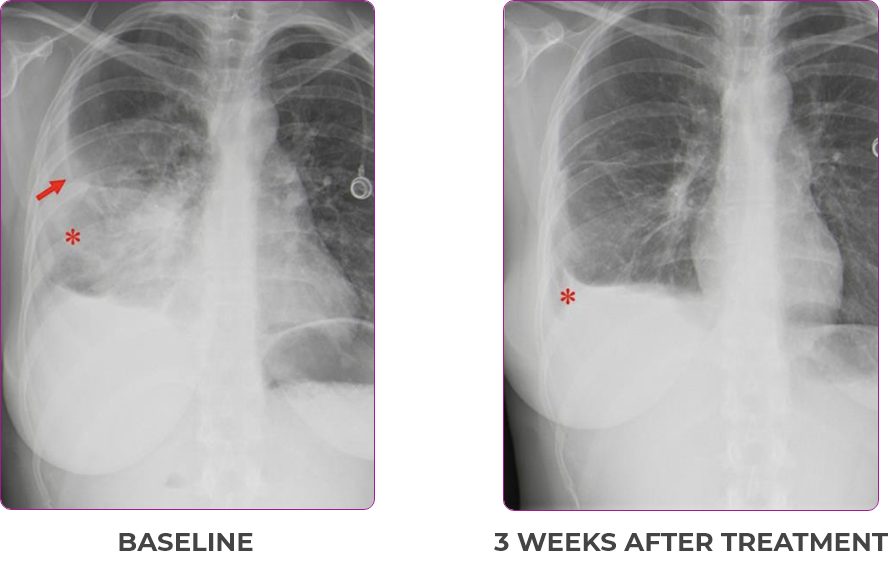

Response in primary and metastatic lesions1

MRIa imagery of the lungs. Arrow indicates large target lesion in left lung.1

SCAN 1: LUNG

MRIa imagery of the brain. Arrow indicates large target lesion in left lung.1

aMRI, magnetic resonance imaging.

Images courtesy of Dr Fabian Pitoia.

- Partial response and symptom improvement confirmed by chest X-rays after <1 month of treatment

- Imaging performed 6 weeks into treatment revealed considerable decrease in the size of both target lesions

Lung imaging of primary tumors.

SCAN 2: LUNG AND BONE

Images courtesy of Dr Maximilian Hochmair.